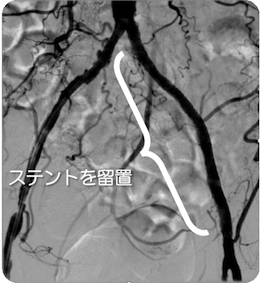

治療前

治療後

血管造影

左腸骨動脈が完全閉塞しており、左下肢の冷感、痛みを認めました。ステントを留置しいずれの症状も消失しています。